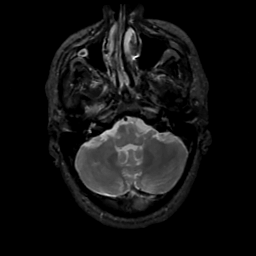

MR Study #3, February 24, 1991 -- Slice #10

[Home][Help][Clinical][Tour 1][Tour 2] Slice 10